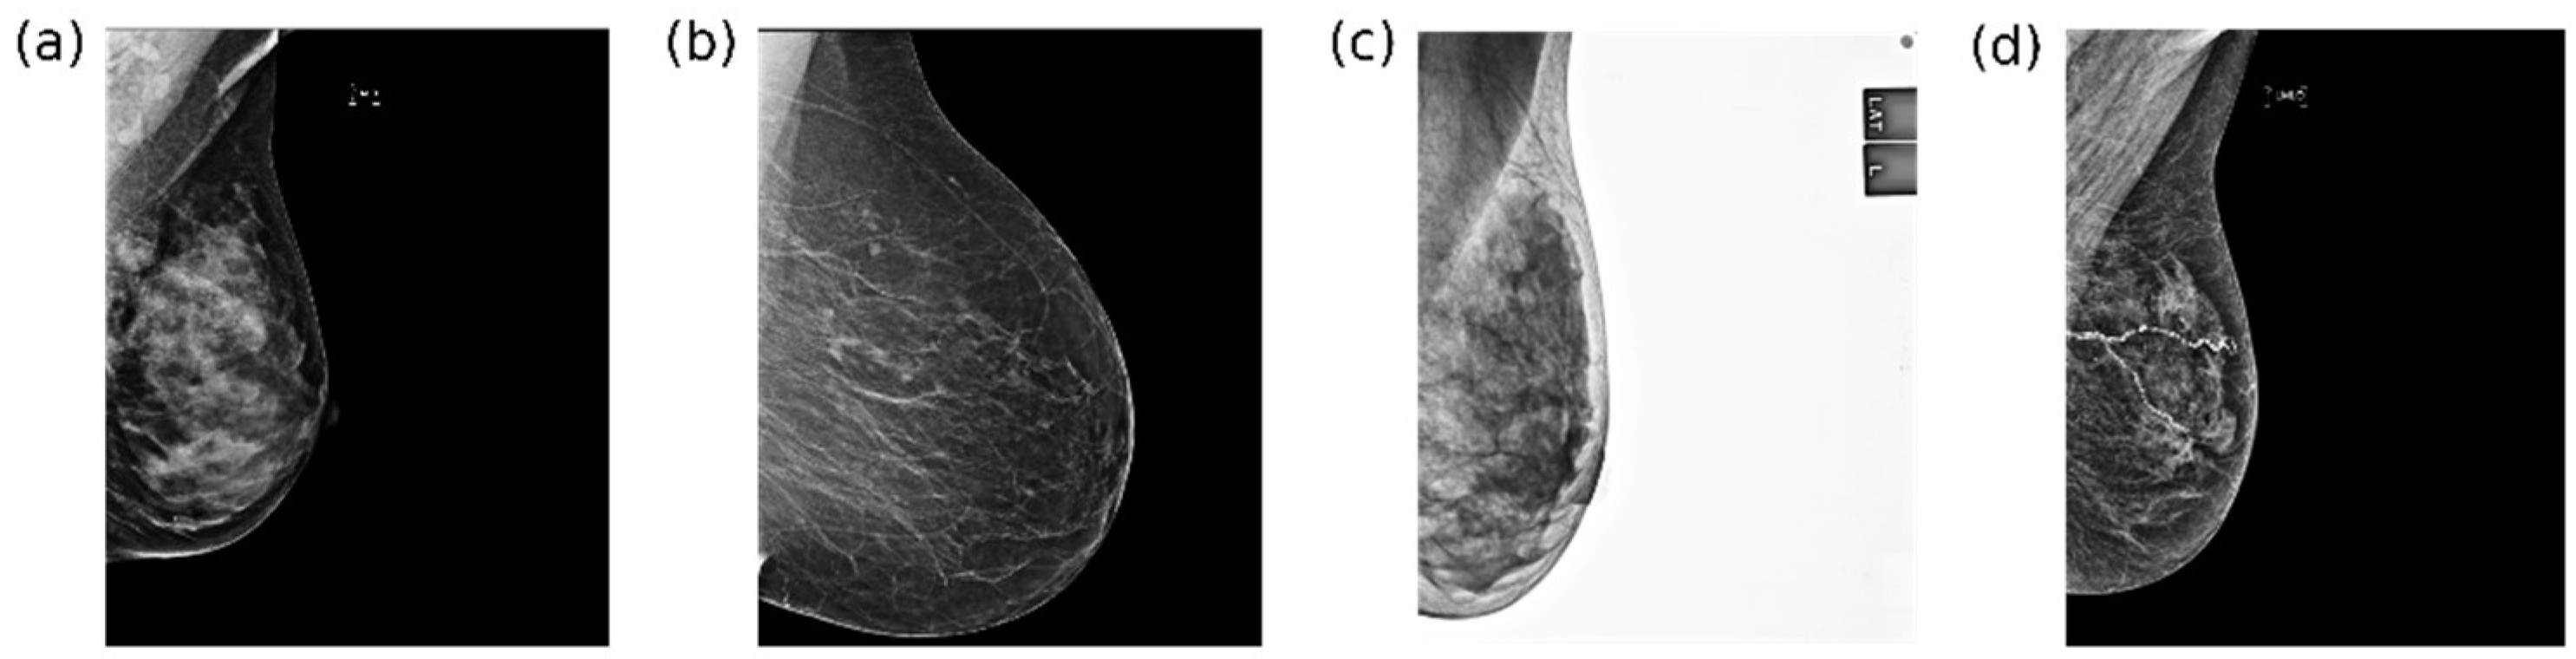

5.2. Preliminary Results—Initial Analysis on Mammography

5.2.1. Data Quality and Related Pre-Processing

5.2.2. Annotation Style